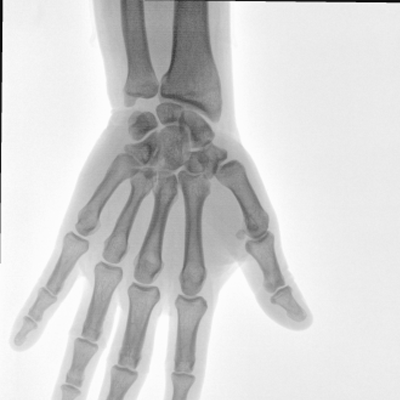

大尺寸動態(tài)平板探測器,高DQE、低噪聲、圖像清晰。采用多分辨率圖像增強處理技術(shù),不同部位不同圖像處理算法,滿足客戶多樣化的需求。